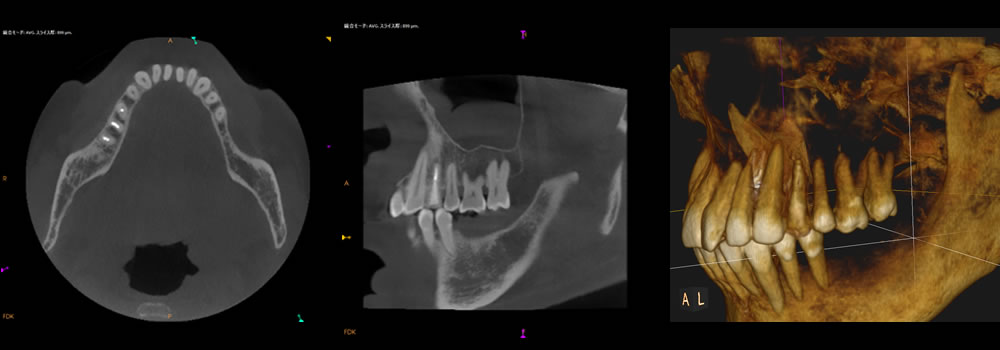

左下奥歯にインプラントを埋入した後のCT画像です。骨造成によって骨が再生し、インプラントが安定しています。